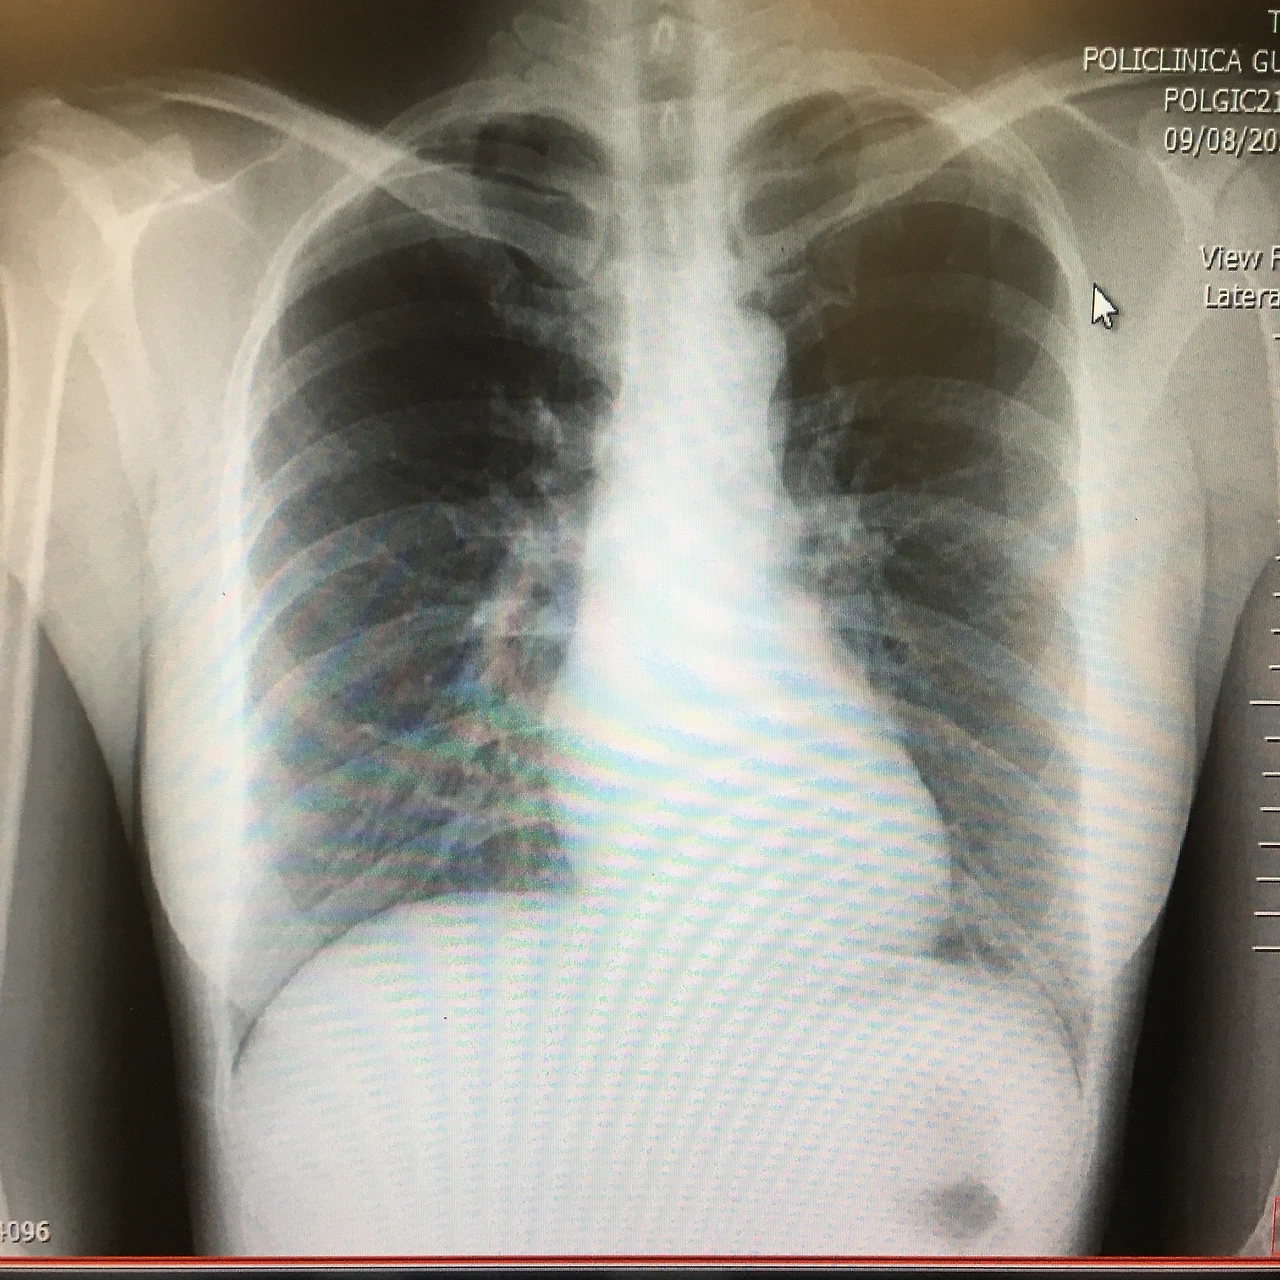

옅게 폐렴이 생겼지만, 그래도 (내 눈엔) 정상처럼 보이는 내 폐

제일 걱정되고 스트레스받던 부분은 이거다. 코로나 확진 판정을 받고 다음 날, 폐렴이 생긴 걸 알았을 때 정말 억장이 무너져내리는 느낌이었고 ‘폐는 한 번 망가지면 복구가 되지 않는다’라는 말을 들었기에 가장 걱정하는 부분이 ‘폐’였기 때문